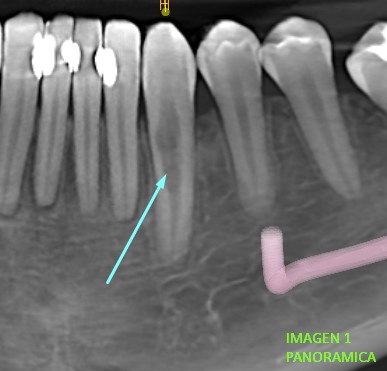

​Luego realizada la tomografía se puede visualizar en la imagen de vista panorámica (imagen 1.), una forma irregular del canal radicular de pieza dentaria 33 a comparación de piezas dentarias aledañas.